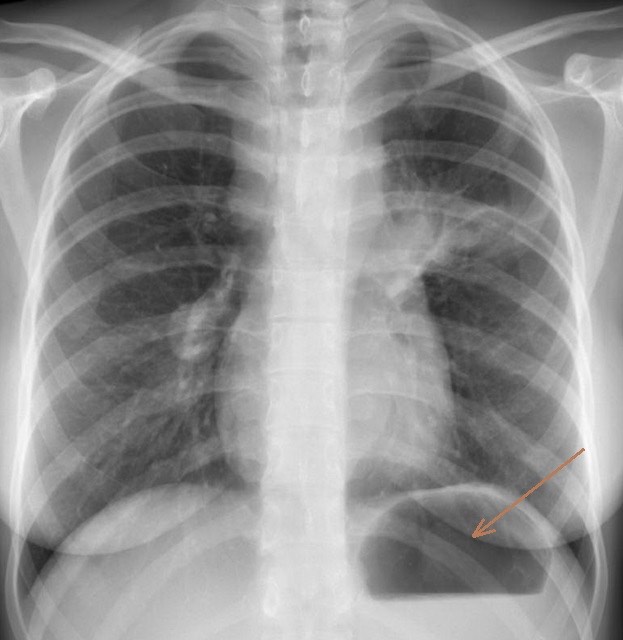

2933. Стрелкой на снимке органов грудной полости в прямой проекции отмечен